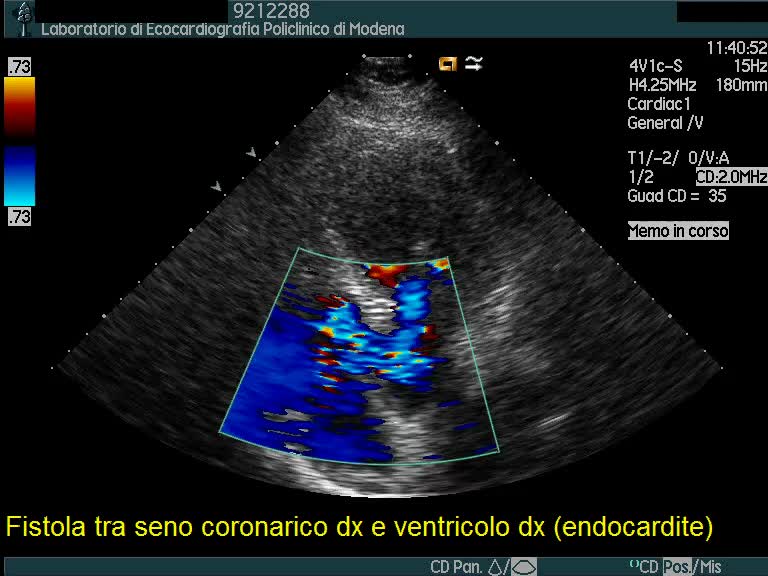

Endocardite infettiva complicata da fistola tra seno coronarico destro e ventricolo destro